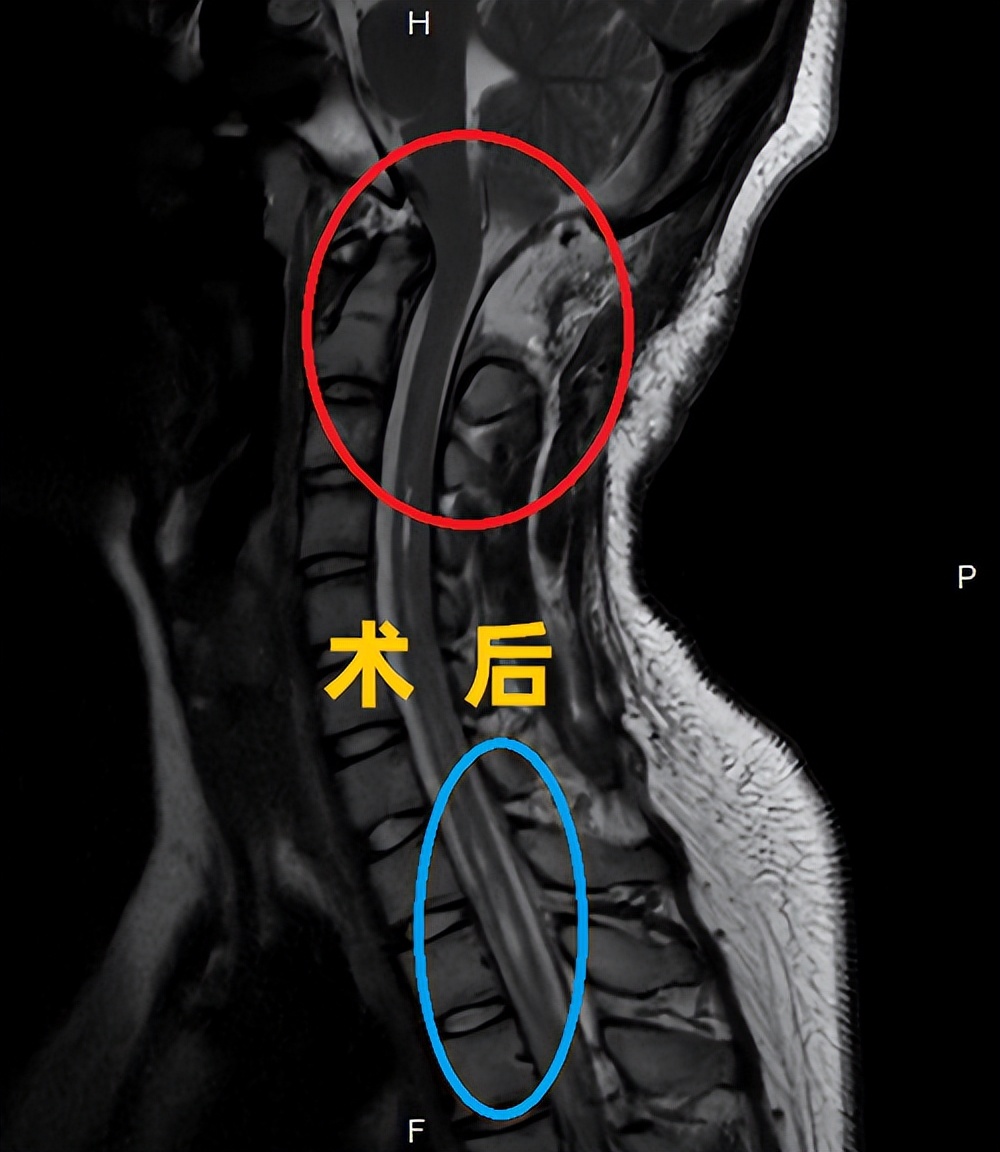

术后影像学资料:

(术后,蓝圈内脊髓空洞明显缩小,红圈为小脑扁桃体下移明显好转)